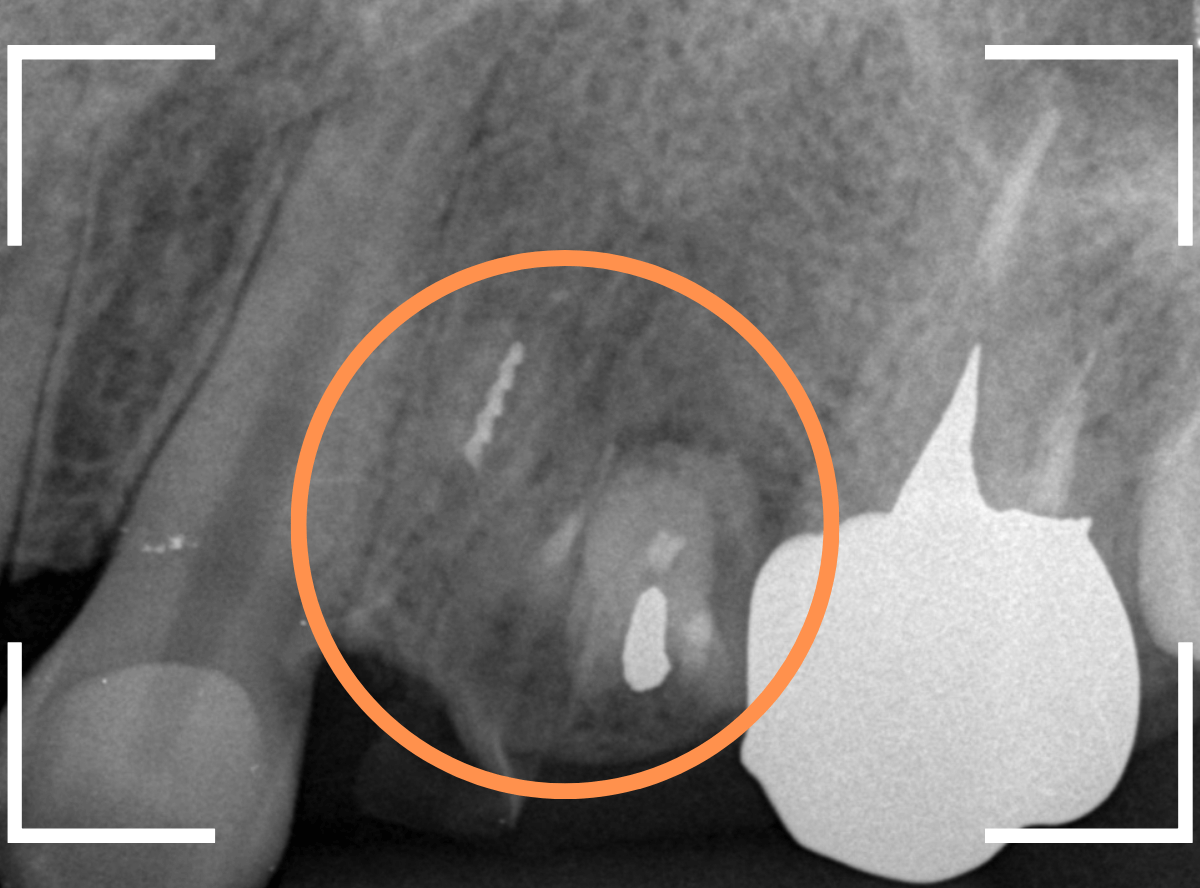

レントゲン写真で確認します。

青い線が歯の形と神経です。

赤い線が、虫歯です。

初見でも想像がつきましたが、かなり虫歯がひどく、治療して再び噛む事が出来るようにするのが不可能で、抜歯をする事になりました。

しかし、レントゲン写真で確認すると、実際には虫歯でボロボロで、歯の根っこだけの状態なのがわかります。

残念ながら抜歯が必要ですが、抜歯も難しくなる可能性が高いケースです。

レントゲン写真でも、ほとんど残ってる歯が確認できません(残根状態(歯の根っこだけ残っている状態)といいます)。

これでは、抜くのも大変そうです(><)